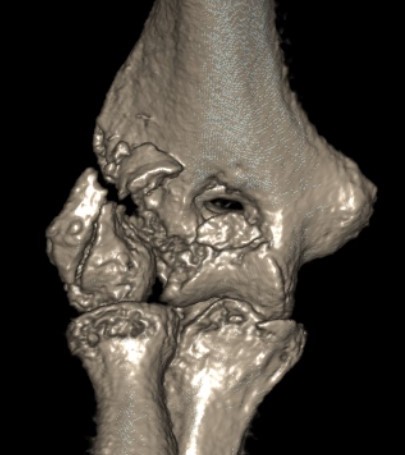

Coronal shear fracture of the distal humerus

Capitellum +/- trochlea

Dubberly Classification

Type I Type Ii Type III

Capitellar fracture

Capitellum + trochlea fracture

In one piece

Capitellum + trochlea fractures

In two separate pieces

Double arc sign on xray